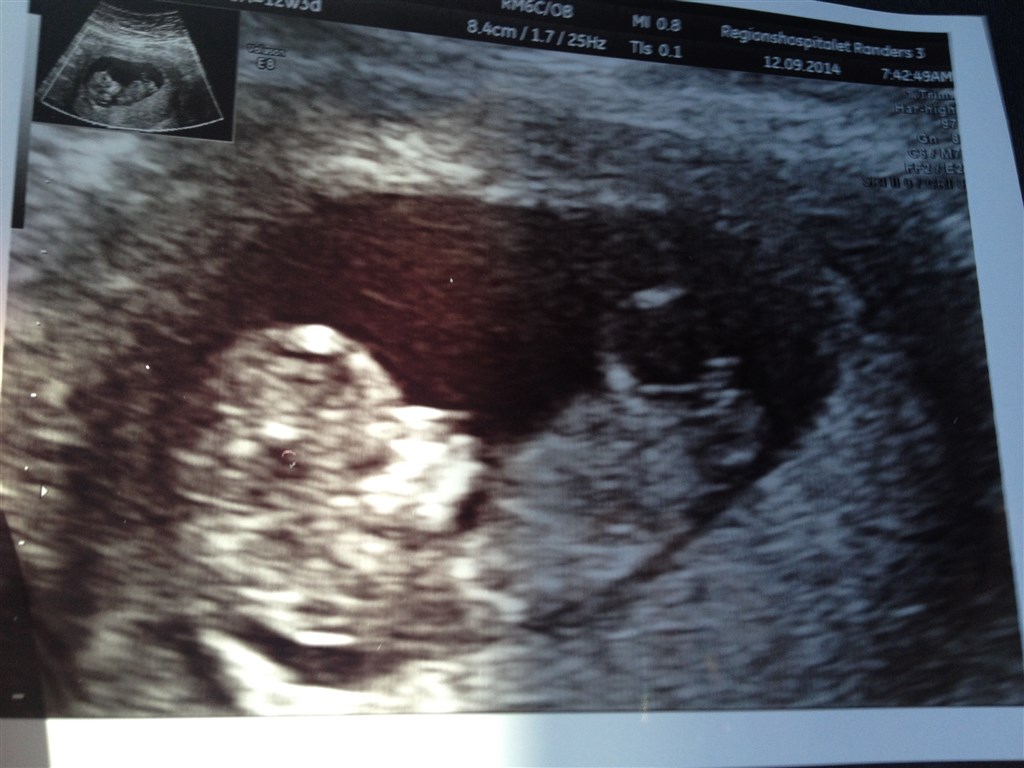

Jeg var til NF i fredags hvor jeg så en livlig lille baby, der helt og aldeles smeltede mit hjerte

Vedhæftede fotos (klik for at se i fuld størrelse)